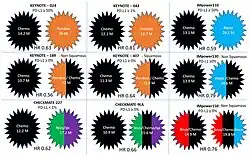

The treatment scenario for patients with resectable non-small cell lung cancer has changed dramatically with the incorporation of immunotherapy. The introduction of immunotherapy into treatment algorithms has yielded improved clinical outcomes in several phase II and III trials in both adjuvant (Impower010 and PEARLS) and neoadjuvant settings (JHU/MSK, LCMC3, NEOSTAR, Columbia/MGH, NADIM,[43] NADIM II[44][45] and CheckMate-816), leading to new U.S. Food and Drug Administration approvals in this sense.

NSCLC cells expressing programmed death-ligand 1 (PD-L1) could interact with programmed death receptor 1 (PD-1) expressed on the surface of T cells and result in decreased tumor cell kill by the immune system. Atezolizumab is an anti-PD-L1 monoclonal antibody. Nivolumab and Pembrolizumab are anti-PD-1 monoclonal antibodies. Ipilimumab is a monoclonal antibody that targets Cytotoxic T-lymphocyte-associated protein 4 (CTLA-4) on the surface of T cells. Bevacizumab is a monoclonal antibody that targets the Vascular Endothelial Growth Factor (VEGF) in the circulation and functions as an angiogenesis inhibitor. Multiple phase 3 clinical trials utilizing immunotherapy in the first line for treatment of NSCLC were published, including Pembrolizumab in KEYNOTE-024, KEYNOTE-042, KEYNOTE-189 and KEYNOTE-407; Nivolumab and Ipilimumab in CHECKMATE-227 and CHECKMATE 9LA; and Atezolizumab in IMpower110, IMpower130 and IMpower150.[60]

The prognosis of patients with non-small-cell lung cancer improved significantly with the introduction of immunotherapy.[60] People with tumor PDL-1 expressed over half or more of the tumor cells achieved a median overall survival of 30 months with pembrolizumab.[64][65]